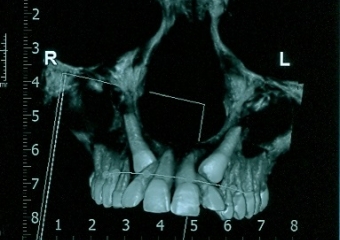

Tomografia - caninos inclusos

Caninos decíduos (de leite)